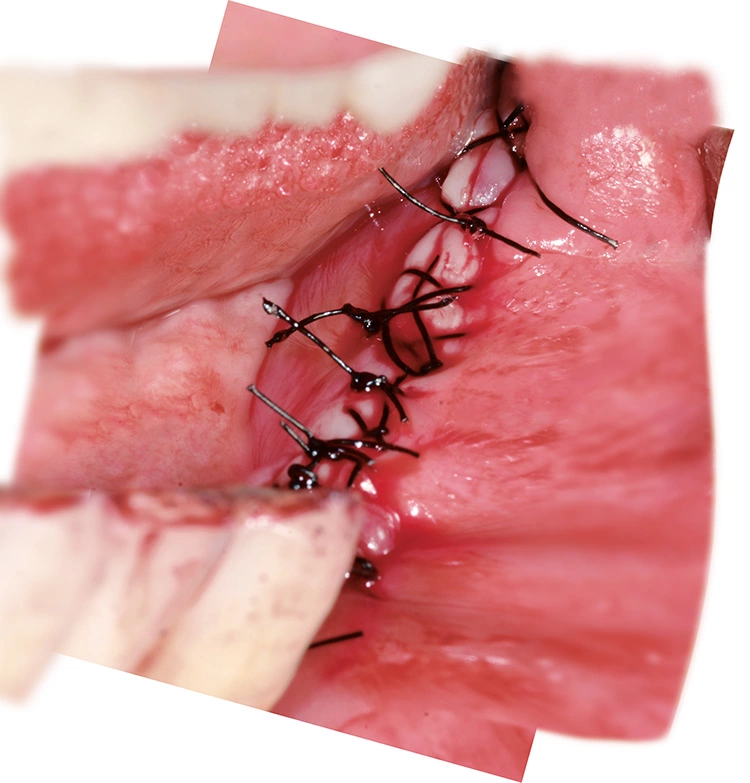

Implantation: 7 Monate nach Augmentation

Trotz der schlechten, hart- und weichgewebigen Grundvoraussetzungen konnte der Kieferkamm zufriedenstellend rekonstruiert werden. Die Augmentation des kombinierten, horizontalen und vertikalen Defekts mit Yxoss CBR®, Geistlich Bio-Oss®, Geistlich Bio-Gide®, autologem Knochen und PRF ermöglichte die Implantation mit hoher Primärstabilität in den rekonstruierten Bereich.